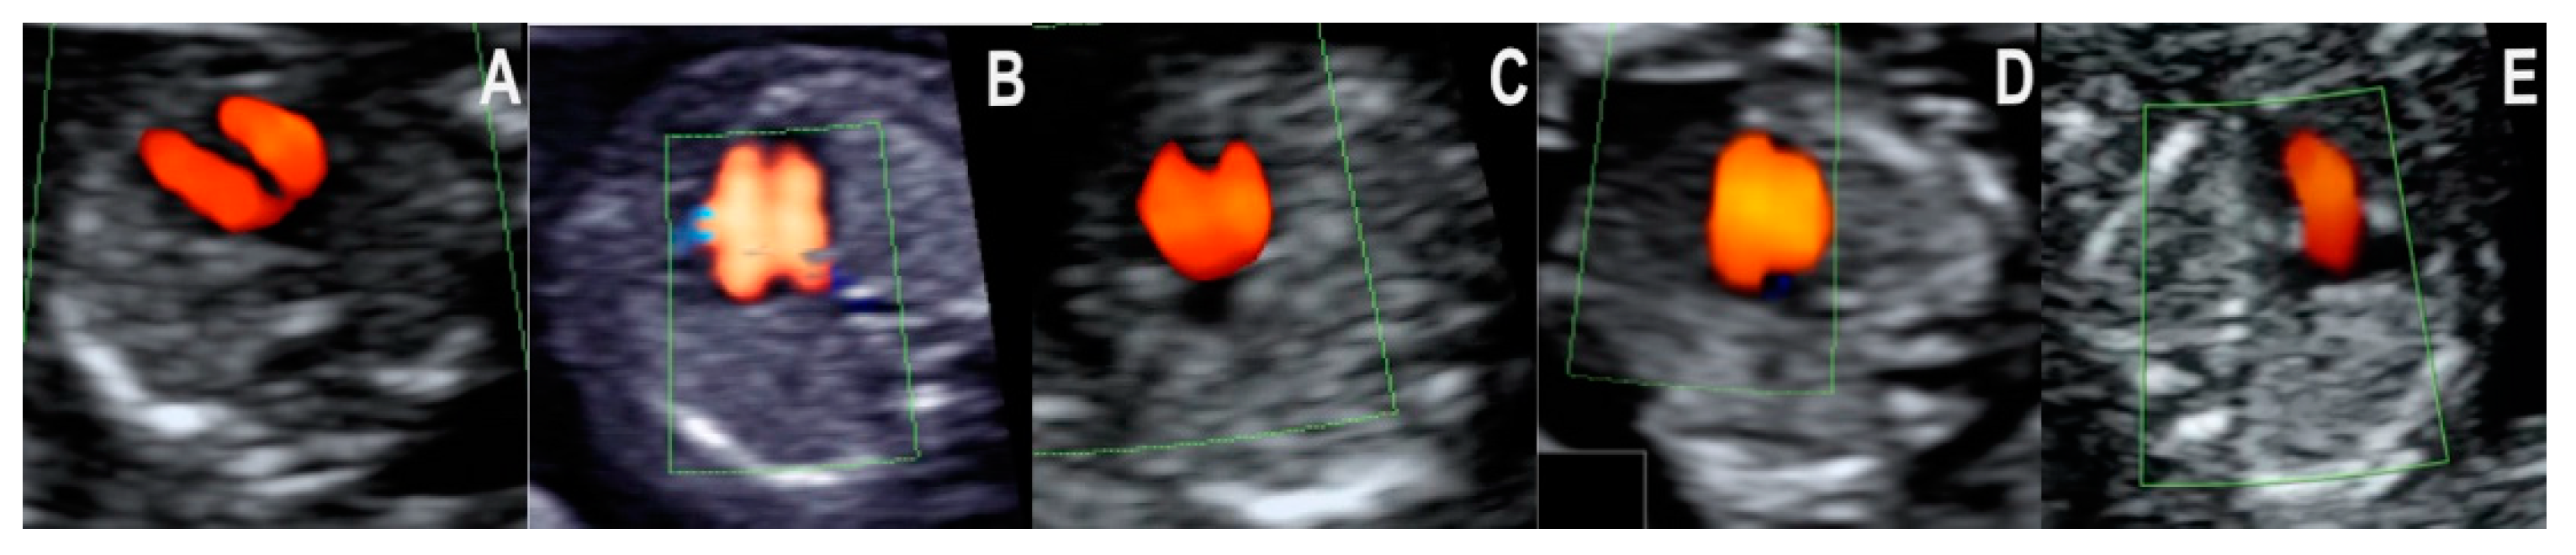

- Normal diastolic filling of both ventricles, with normal cardiac axis and two equally sized great vessels with normal antegrade flow, forming a V sign. This pattern was seen in all of the 20 cases with a structurally normal heart. The pattern’s negative predictive value for CHD that needs major surgical correction after birth is likely high, but little evidence is available to support this hypothesis. Isolated totally anomalous pulmonary veins return, and minor structural defects (e.g., ventricular septal defect, VSD), evolving lesions (e.g., mild valvular stenosis, tumors), or defects that are only postnatally diagnosed (e.g., atrial septal defect, ASD) might show this pattern in the first trimester.

- Common inflow of both ventricles through a common atrioventricular valve and two equally sized great vessels with normal antegrade flow, forming a V sign. All of the atrioventricular septal defect (AVSD) cases in our series showed this pattern in the first trimester. AVSD with situs solitus is usually associated with genetic disorders, namely Down syndrome [16,17].

- Distinct filling of both ventricles, but the left ventricle appears shorter (smaller), and two unequal vessels form the V sign (one vessel narrower). All the four cases of coarctation of the aorta (CoAo) seen in the first trimester showed this pattern. This type of CHD is a progressive disease. In our experience, the cases suspected in the first trimester are usually severe.